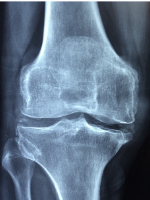

무릎 관절염 치료방법

무릎 관절염을 치료하는 방법에는 보존적 치료와 수술적 치료가 있습니다. 보존적 치료는 약물, 물리치료, 생활습관 개선 등으로 이루어지며, 초기 단계의 관절염에 적용됩니다. 수술적 치료는 인공관절 수술이나 골수 줄기세포 재생술 등으로 이루어지며, 보존적 치료로 증상이 호전되지 않거나 중증도의 관절염에 적용됩니다.

보존적 치료의 방법은 다음과 같습니다.

1) 약물: 통증과 염증을 완화하기 위해 항염증제나 스테로이드 주사를 사용할 수 있습니다. 항염증제는 구강제나 외용제로 사용할 수 있으며, 스테로이드 주사는 관절 내 주입을 할 수 있습니다. 약물은 장기간 사용하면 부작용이 있을 수 있으므로 의사와 상의하여 적절한 용량과 기간을 정해야 합니다.

2) 물리치료: 통증과 염증을 줄이고 근육과 인대를 강화하기 위해 물리치료를 시행할 수 있습니다. 물리치료에는 온찜질, 전기치료, 초음파치료, 도수치료 등이 있습니다. 온찜질은 온도가 낮은 핫팩을 무릎에 얹어서 혈액 순환을 촉진하고 근육을 이완시키는 방법입니다. 전기치료는 경피신경자극(TENS)이나 근육자극(NMES) 등으로 전기 자극을 주어 통증을 완화하고 근육을 강화하는 방법입니다. 초음파치료는 고주파를 이용하여 열을 통증 부위에 전달하고 마사지 효과를 주는 방법입니다. 도수치료는 발목 펌프 운동, 정면 다리 올리기 운동, 측면 다리 올리기 운동, 와이드 스쿼트 운동 등으로 구성되며, 무릎 관절의 운동 범위를 늘리고 허벅지 근육을 강화하는 방법입니다.

3) 생활습관 개선: 체중을 감소시키고, 무릎에 과부하를 주는 운동이나 자세를 피하는 것이 중요합니다. 체중이 많이 나가면 무릎에 가해지는 압력이 증가하므로, 적절한 식사와 운동으로 체중을 조절해야 합니다. 무릎에 과부하를 주는 운동은 달리기, 계단 오르내리기, 스쿼트 등이 있으며, 이런 운동은 피하고 평지 걷기, 자전거 타기, 수영 등의 저충격 운동을 하는 것이 좋습니다. 무릎을 많이 구부리는 방바닥 생활이나 쪼그리기도 피하고, 가급적 의자를 이용하거나 무릎에 쿠션을 놓는 것이 바람직합니다.

수술적 치료의 방법은 다음과 같습니다.

1) 인공관절 수술: 무릎 관절의 연골과 뼈가 심하게 손상되어 보존적 치료로 증상이 호전되지 않는 경우에 시행하는 수술입니다. 손상된 무릎 관절을 잘라내고 인공관절로 대체하는 방법으로, 통증을 완전히 없애주고 관절의 기능을 회복시켜줍니다. 인공관절 수술은 전신마취와 부분마취 중 선택할 수 있으며, 수술 시간은 약 1~2시간 정도입니다. 수술 후에는 일정 기간의 입원과 재활치료가 필요합니다.

2) 골수 줄기세포 재생술: 무릎 연골이 닳아서 뼈가 드러난 부위에 골수 내 줄기세포가 이동하여 연골세포로 재생되게 하는 수술입니다. 부분마취만을 시행한 후, 정밀 초음파나 미세침 내시경으로 손상된 연골 부위를 확인합니다. 이후 연골손상 부위의 뼈에 1mm 크기의 미세한 구멍을 여러 개 만들어서 골수가 흘러나오도록 합니다. 골수가 수 개월 동안 흘러나오면서 골수에 포함된 줄기세포 성분이 손상된 연골세포로 분화하게 됩니다. 골수 줄기세포 재생술은 시술 시간이 총 30분 정도여서 당일 시술 및 퇴원이 가능하고 바로 일상생활을 할 수 있습니다.

무릎 관절염은 일단 발생하면 저절로 치유되지 않는 질환입니다. 따라서 초기에 적절한 치료와 관리를 해주어야 합니다. 위에서 소개한 치료 방법들은 모두 환자의 상태와 증상에 따라 달라집니다. 따라서 정확한 진단과 치료 계획을 위해서는 전문적인 의사와 상의하는 것이 필요합니다.